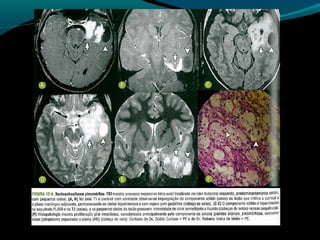

Astrocitoma pilocítico

TC:

Tumor circunscrito sólido cístico

Lesão infiltrativa intra ou extraorbitária

Componente sólido iso ou hipodenso e realce pelo

contraste;

Em até 20% pode ser totalmente sólido;

Calcificações em até 20%;

Diencéfalo;

RM

Iso ou hipointenso em T1 e hiper em T2;

Realce difuso pelo Gd;

Paredes do componente cístico: podem ter realce pelo

Gd;

Edema perilesional é incomum;